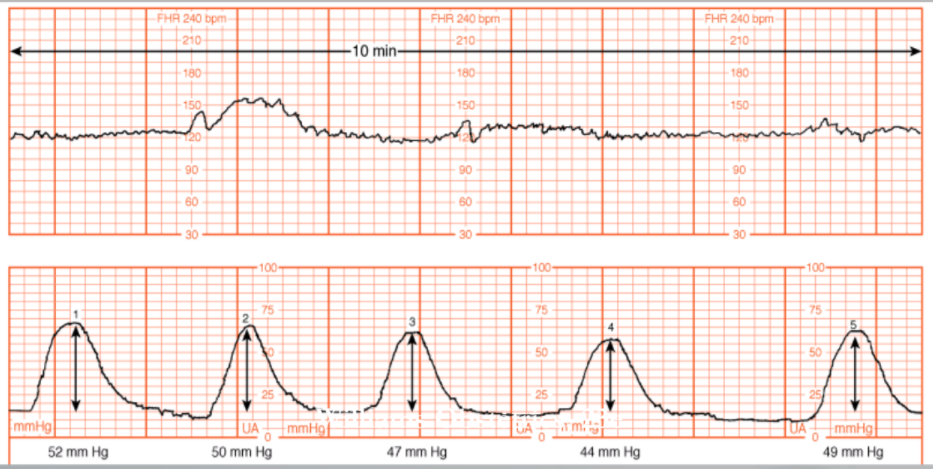

• Calculation derived from subtracting the baseline uterine pressure from the peak contraction pressure for each contraction in a 10-min. window and adding the pressures generated by each contraction. In the example shown, there were 5 contractions, producing pressure changes of 52, 50, 47, 44 and 49 mm HG, respectively. The sum of these 5 contractions is 242 Montevideo units